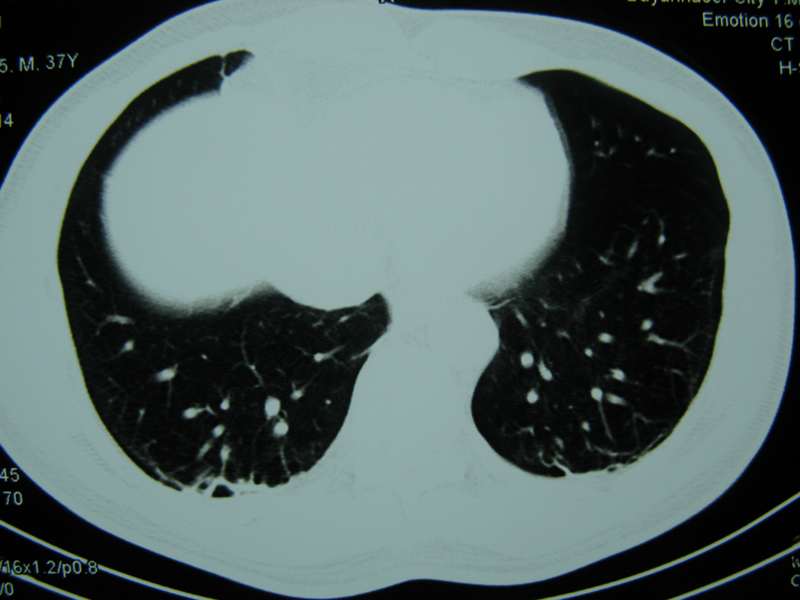

男,37岁,主述胸疼厉害,无咳嗽,无发热,血象也不高,病灶内ct值脂肪密度,右侧胸腔内少量积液,同道们考虑什么?谢谢!

两肺下叶基底段纤维灶,右肺下叶基底背侧相应胸膜肥厚,右肺中叶内侧段部分不张。前中下纵隔团块状脂肪影,随访除外胸腺脂肪瘤。